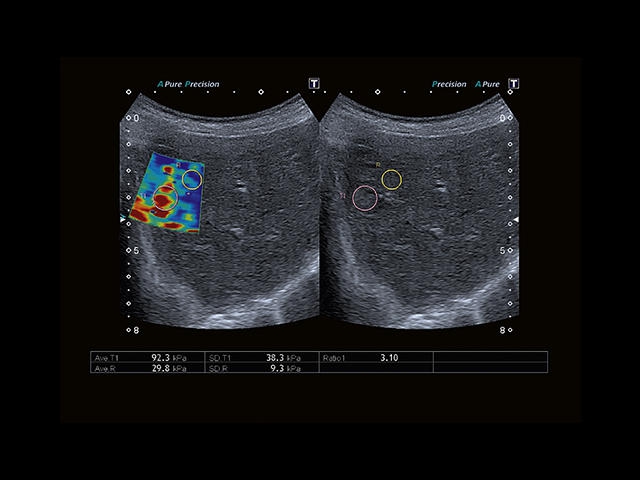

Обновленная версия легендарного УЗ-сканера. Стационарный аппарат экспертного класса Aplio 500 Toshiba NEW, визуализирует анатомические структуры в высоком разрешении. Модель позволяет выявить микрокальцификаты, новообразования, нарушения в работе сердца, сосудов и мышц. Присутствует функция виртуальной эндоскопии, 4D-сканирования, эластометрии тканей, УЗИ с контрастированием. За повышение качества изображения отвечают технологии ApliPure и Superb Microvascular Imaging. Первая задействует возможности пространственного и частотного кодирования, формирует цельный визуальный ряд с сохранением клинических маркеров. Вторая улучшает отображение микрососудистого русла, используя доплеровский эффект. Модель оснащена 21-дюймовым монитором, имеет 4 активных порта. Возможно подключение педиатрических, интраоперационных, лапароскопических и чреспищеводных датчиков.

Эластография:

Компрессионная

Эластография сдвиговой волной/Эластометрия:

Компрессионная эластография:

Да